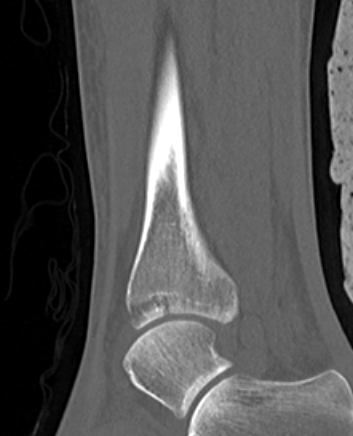

Posterior Malleolar Fractures

- occult in 70%

- especially with spiral distal tibial fractures

Posterior malleolar fixation

Typically stabilize intra-articular fracture first

- intra-articular extension